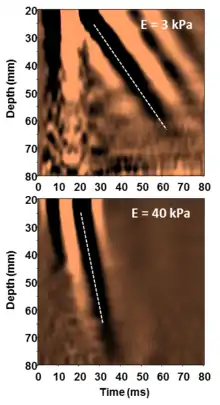

Shear-wave elasticity imaging (SWEI)

In shear-wave elasticity imaging (SWEI),[7] similar to ARFI, a 'push' is induced deep in the tissue by acoustic radiation force. The disturbance created by this push travels sideways through the tissue as a shear wave. By using an image modality like ultrasound or MRI to see how fast the wave gets to different lateral positions, the stiffness of the intervening tissue is inferred. Since the terms "elasticity imaging" and "elastography" are synonyms, the original term SWEI denoting the technology for elasticity mapping using shear waves is often replaced by SWE. The principal difference between SWEI and ARFI is that SWEI is based on the use of shear waves propagating laterally from the beam axis and creating elasticity map by measuring shear wave propagation parameters whereas ARFI gets elasticity information from the axis of the pushing beam and uses multiple pushes to create a 2-D stiffness map. No shear waves are involved in ARFI and no axial elasticity assessment is involved in SWEI. SWEI is implemented in supersonic shear imaging (SSI).

Supersonic shear imaging (SSI)

Supersonic shear imaging (SSI)[8][9] gives a quantitative, real-time two-dimensional map of tissue stiffness. SSI is based on SWEI: it uses acoustic radiation force to induce a 'push' inside the tissue of interest generating shear waves and the tissue's stiffness is computed from how fast the resulting shear wave travels through the tissue. Local tissue velocity maps are obtained with a conventional speckle tracking technique and provide a full movie of the shear wave propagation through the tissue. There are two principal innovations implemented in SSI. First, by using many near-simultaneous pushes, SSI creates a source of shear waves which is moved through the medium at a supersonic speed. Second, the generated shear wave is visualized by using ultrafast imaging technique. Using inversion algorithms, the shear elasticity of medium is mapped quantitatively from the wave propagation movie. SSI is the first ultrasonic imaging technology able to reach more than 10,000 frames per second of deep-seated organs. SSI provides a set of quantitative and in vivo parameters describing the tissue mechanical properties: Young's modulus, viscosity, anisotropy.

Transient elastography was initially called time-resolved pulse elastography[15] when it was introduced in the late 1990s. The technique relies on a transient mechanical vibration which is used to induce a shear wave into the tissue. The propagation of the shear wave is tracked using ultrasound in order to assess the shear wave speed from which the Young's modulus is deduced under hypothesis of homogeneity, isotropy and pure elasticity (E=3ρV²). An important advantage of transient elastography compared to harmonic elastography techniques is the separation of shear waves and compression waves.[16] The technique can be implemented in 1D [17] and 2D which required the development of an ultrafast ultrasound scanner.[18]

Transient elastography gives a quantitative one-dimensional (i.e. a line) image of "tissue" stiffness. It functions by vibrating the skin with a motor to create a passing distortion in the tissue (a shear wave), and imaging the motion of that distortion as it passes deeper into the body using a 1D ultrasound beam. It then displays a quantitative line of tissue stiffness data (the Young's modulus).[19][20] This technique is used mainly by the Fibroscan system, which is used for liver assessment,[21] for example, to diagnose cirrhosis.[22] A specific implementation of 1D transient elastography called VCTE has been developed to assess average liver stiffness which correlates to liver fibrosis assessed by liver biopsy.[23][24] This technique is implemented in a device which can also assess the controlled attenuation parameter (CAP) which is good surrogate marker of liver steatosis.[25]